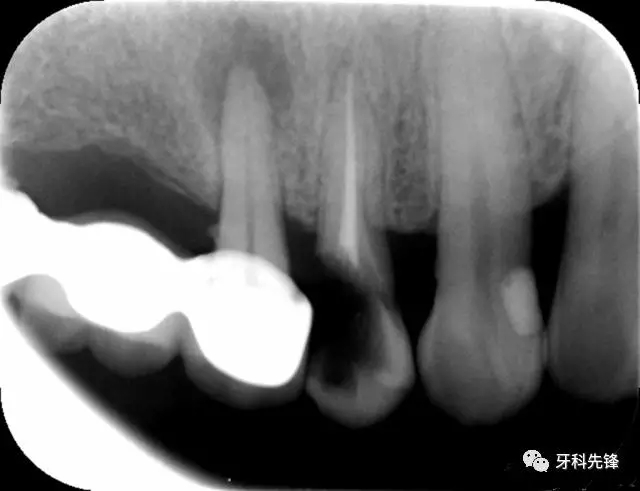

X 示:15  根管透射,根尖有陰影

14  根管阻射,恰填,無異常

46  根管阻射,恰填,根分叉骨密度降低,近中根尖陰影較大

圖1 術前X光片